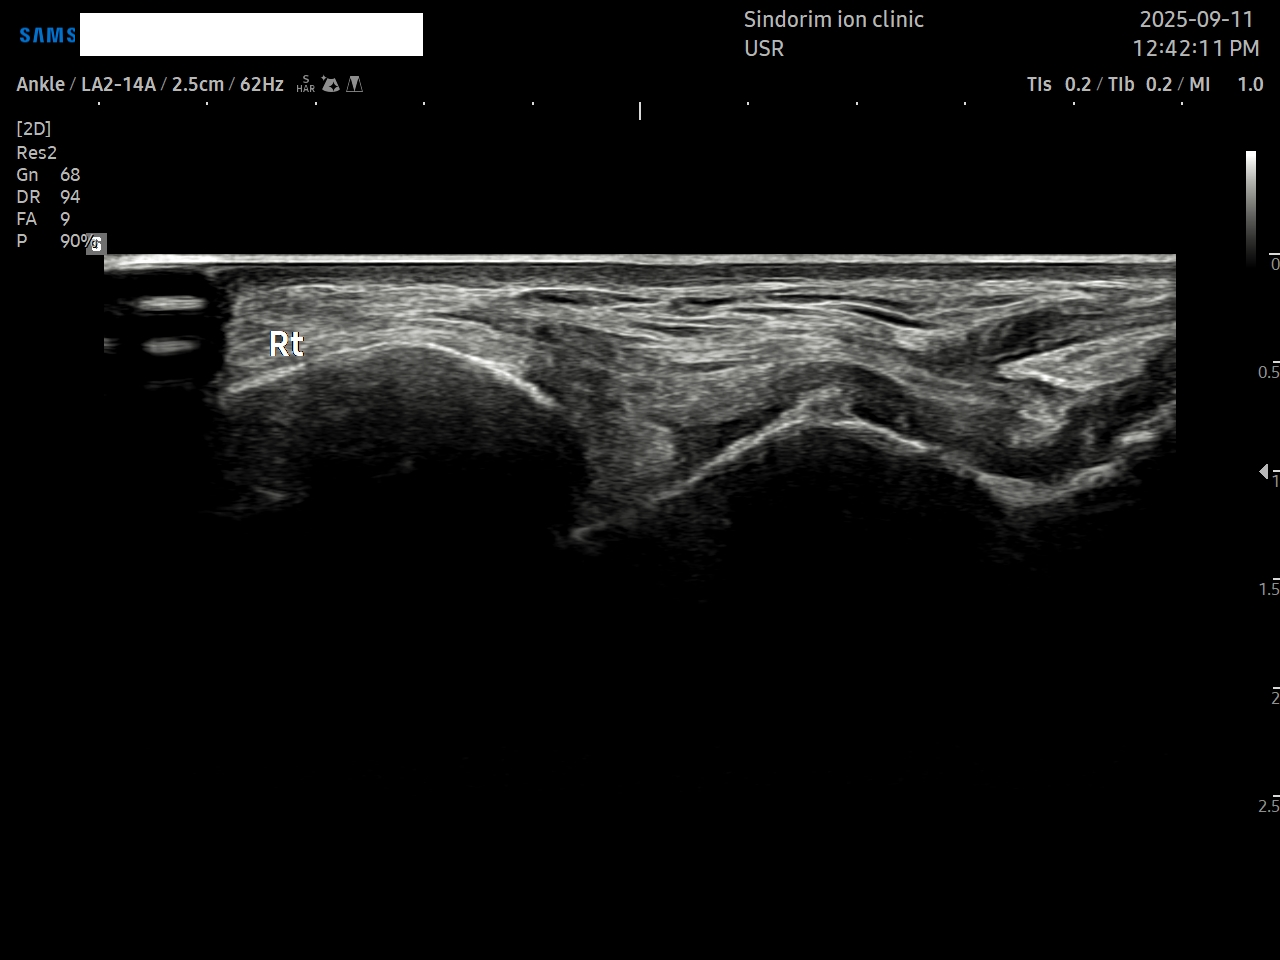

- 치료기간 : 25 . 5 . 3 ~ 25 . 9 . 11

- 치료횟수 : 10 회 (2 cycle)

우측 발 (치료 전 → 후)